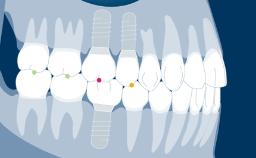

Implants and their prostheses replace teeth.

They therefore have to participate fully in oral function. A substantial part of oral function is related to occlusion when the teeth and their replacements make contact.

- recognize characteristics of occlusal forces and biophysical differences in how teeth and implants respond to them